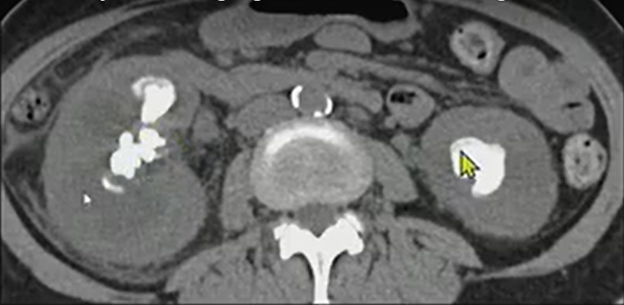

Xanthogranulomatous pyelonephritis (XGP) is a rare, destructive renal infection, most often in women with staghorn calculi. It replaces functioning parenchyma with lipid-laden macrophages and inflammatory tissue, often extending beyond the kidney.

- Classic appearance: Enlarged kidney, staghorn calculi, and a contracted pelvis—the “bear paw.”

When you see that “bear paw” (i.e., staghorn calculus, perinephric inflammation, and an enlarged, poorly functioning kidney), think XGP!